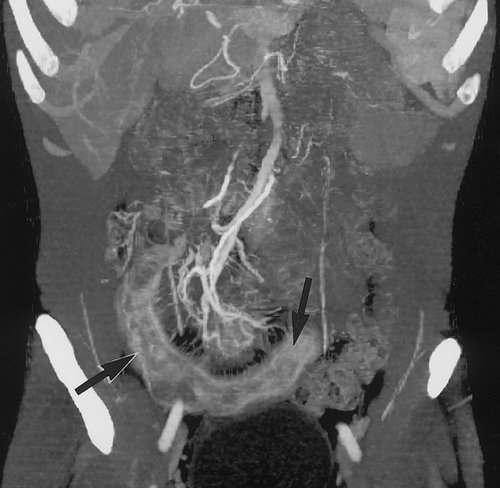

The introduction of multidetector CT with three-dimensional rendering may provide unique capabilities for this application (Fig 5). The presence of SMA or SMV stenosis or occlusion, narrowing or occlusion of proximal or distal mesenteric branch vessels, and patterns of collateralization can be clearly defined with this technique (Fig 6). The use of both volume rendering and MIP-based three-dimensional reconstruction allows the branching of the mesenteric vessels to be defined in similar or better detail compared with classic angiography without the need for catheter placement. An additional advantage of CT angiography over conventional angiography is the ability to evaluate bowel enhancement. In cases of ischemia, there are often changes in bowel enhancement, which may be seen as focal decreased enhancement of the small bowel on the CT images (18).

Our experience with multidetector CT angiography shows the need for dual-phase acquisitions. The arterial-phase acquisition is best for arterial mapping, especially of smaller more distal branch vessels, whereas the venous phase is best for defining SMV patency and the patency of the portal vein, inferior mesenteric vein, and its tributaries. The later phase images are also best for detecting changes in bowel enhancement in ischemia.

Another potential application that we believe may be developed with multidetector CT and CT angiography is a more functional examination of the bowel in Crohn disease (Fig 7). Although CT has long been used to determine the extent of Crohn disease involvement especially for extraluminal disease, the question of disease activity has always been a challenge. If the bowel is thickened, it is simply a sign of Crohn disease but not an indicator of activity. Preliminary work suggests that we may be able to obtain additional information from CT angiography about disease activity. We have found two important signs at dual-phase CT angiography that may suggest active disease. First, the distant arterial branches to bowel appear dilated and often serpentine. Second, the areas of active disease are increasingly enhanced on the early-phase images, which is probably a result of hyperemia and increased blood flow. Prior reports of ultrasonographic and magnetic resonance imaging findings have suggested that active Crohn disease manifests with increased blood flow. Larger studies with surgical and pathologic correlation will be needed to document the frequency of these findings, and only then will the role of CT angiography in evaluating Crohn disease be clearer.